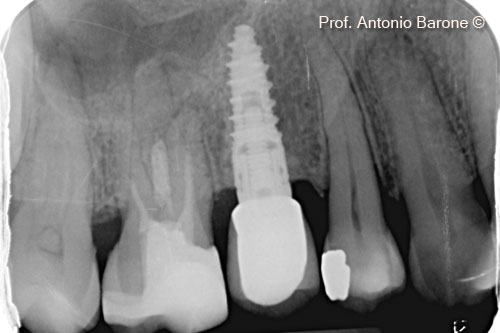

Chụp X-Quang quanh chóp răng kèm đặt implant

Hình ảnh X-Quang chóp răng 1 năm sau khi cấy ghép implant

Hình ảnh X-Quang chóp răng 3 năm sau khi cấy ghép implant